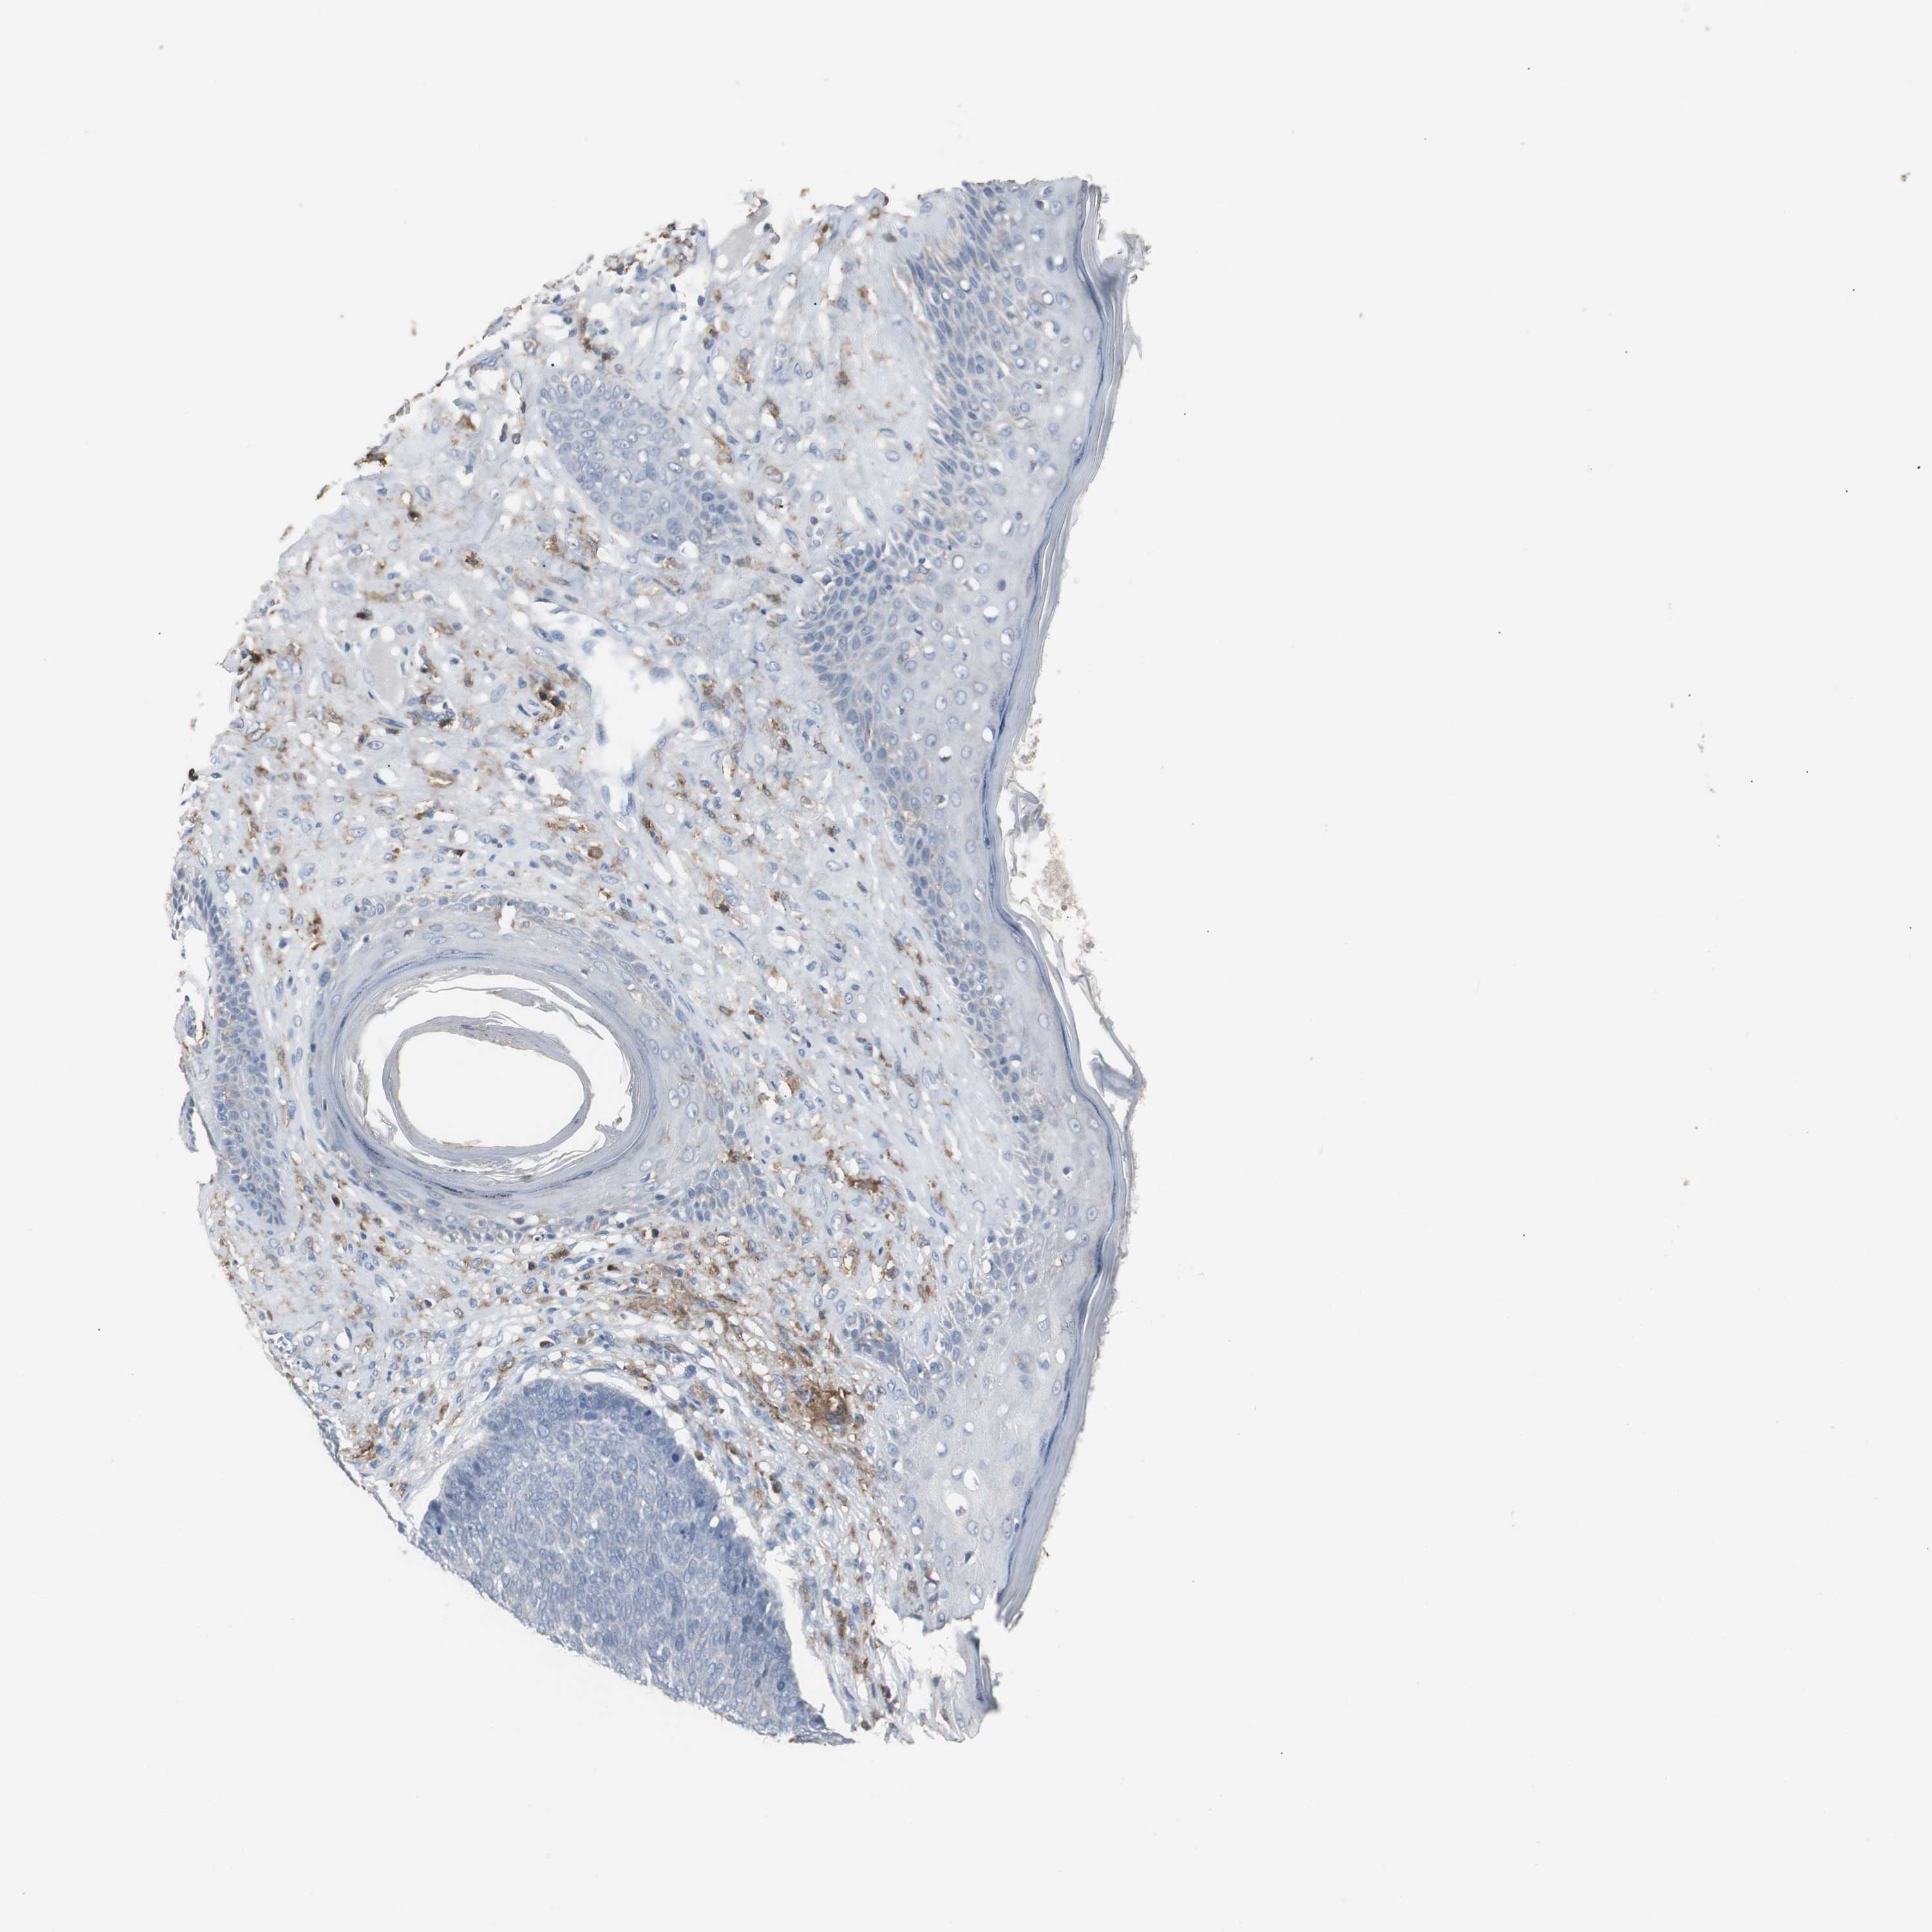

CANCER SKIN CANCER Show tissue menu

Basal cell and squamous cell cancer

SKIN CANCER - Protein expressioni

A mouse-over function shows sample information and annotation data. Click on an image to view it in a full screen mode. Samples can be filtered based on level of antibody staining by selecting one or several of the following categories: high, medium, low and not detected. The assay and annotation is described here.

Each image is clickable and will lead to virtual microscopy that enables deeper exploration of all samples and also displays staining intensity scores, fraction scores and subcellular localization as well as patient and tissue information for each sample.

Antibody HPA002327

Antibody HPA006040

Antibody CAB022160

Squamous cell carcinoma, NOS

Basal cell carcinoma